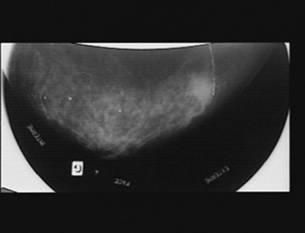

MAMOGRAFIA

2) SEMNAL MIXT FIBRO-CALCIC

Este un semn pe jumatate negativ. Este asocierea unei imagini hipoecogene sau a unei dezorganizari arhitecturale cu con de umbra posterioara variabila ca importanta. Calcificarile produc o oprire progresiva a ultrasunetelor pana la stop ecografic. Conurile de umbra depind de numarul, marimea, repartizarea si densitatea calcificarilor. Microcalcificarile benigne sunt bine percepute prin ultrasonografie; cele maligne nu sunt reperabile decat in primii centimetri cu sondele HRHF de 10 MHz si trebuie sa fie confruntate cu datele mamografice.

50-60 % din cancerele mamare debuteaza prin microcalcificari izolate, fara reactie fibroasa in jurul calcificarii. Aceasta este limita ecografiei in diagnosticul si supravegherea cancerului de san si de aici triumful mamografiei